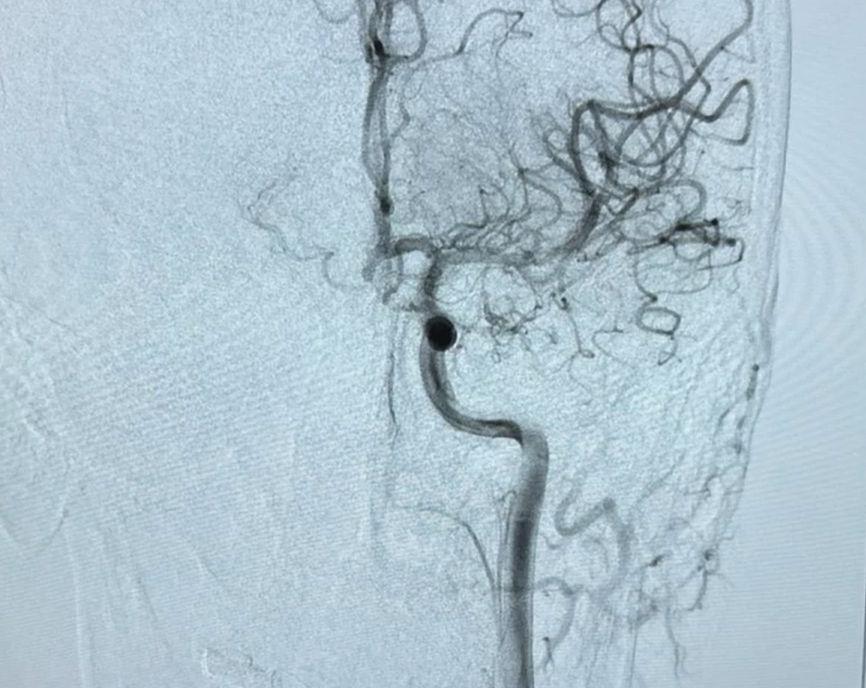

Pacient cu AVC din Cluj, plimbat între cinci spitale din judeţ. A ajuns într-un final la o unitate spitalicească tocmai din Suceava | Imaginea 3 din 6 | Galerie Foto

Pacient cu AVC din Cluj, plimbat între cinci spitale din judeţ. A ajuns într-un final la o unitate spitalicească tocmai din Suceava